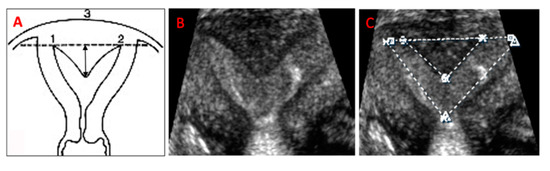

In addition to all the standard measurements obtained with 2-D imaging, including uterine length, height, and width, cavity measurements were obtained on a frozen 3-D coronal view of the uterus. These included the subseptation’s length (measured from the base to the apex) [3,11,20] and width (measured at the subseptation’s base), cavity width (measured at the largest segment between the tubal ostia), and total cavity length (measured from the midpoint between the tubal ostia and the internal os, to include the length of the subseptation, when applicable) (Figure 1). The frozen coronal view was rotated around the x-axis to evaluate the outer contour of the uterus, in order to obtain the most accurate subseptation measurements. All reconstructed mid-coronal images of the uterus encompassed the entire volume of the uterus, including the cervix. For the scans we used two ultrasound machines: Philips XD11 with a 7.5 MHz transvaginal probe and a Samsung UGEO WS80A 3-D with a 7.5 MHz transvaginal probe. One experienced sonologist (LD) performed all the scans and 3-D volume acquisition and analysis. Although patients were prospectively enrolled after diagnosis of a subseptate uterus, the area of the uterine cavity was measured successively, and solely for the purpose of this study. The surface of the uterine cavity was calculated assuming a triangular shape of the cavity: ½ cavity width x cavity length. For subseptate uteri, we subtracted the subseptation surface, again considering an approximately triangular shape of the subseptation: ½ subseptation width x subseptation length. We noted the subseptation shape on the 3-D coronal picture of the uteri and distinguished between V-shaped and U-shaped subseptations, depending on the angle of the indentation’s apex: an angle <90° identifies a V-shaped, while an angle >90° identifies a U-shaped subseptation. To minimize results variability, we performed our scans mostly in the follicular phase and /or with endometrial echoes less than 7 mm in total thickness, to avoid possible area calculation errors. We did not calculate the endometrial volume, because this calculation would be subject to variability, even with a 2–3-mm difference in endometrial thickness.

Figure 1. (A). Graphic representation and 3-D ultrasound measurement technique of uterine subseptations (1,2= left and right tubal ostia; 3= fundal outer contour; arrows: measurement of subseptation length). (B). 3-D ultrasound coronal view rendering of a subseptation. (C). Measurement of the cavity width (12), and subseptation width, for calculation of cavity area on the 3-D ultrasound coronal view.